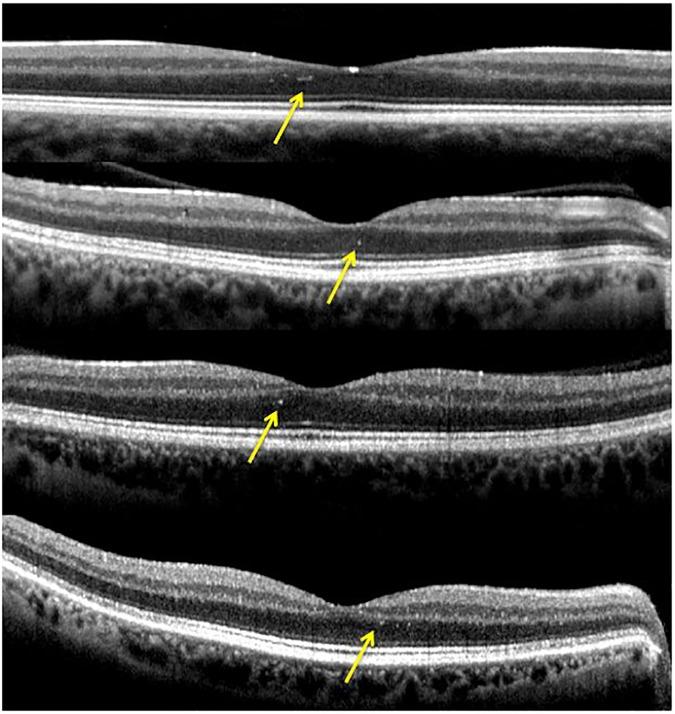

This prospective cross-sectional study included 11 patients with ADOA and 11 age-matched healthy subjects. All participants underwent both a "Posterior Pole" and "peripapillary RNFL (pRNFL)" scanning protocol using SD-OCT. Functional mapping of the PP was also performed using MP. A customized program was implemented in order to achieve accurate superimposition of MP sensitivity map onto SD-OCT map. The thickness of the PP different retinal layers and pRNFL was obtained and measured for each eye. Mean retinal sensitivity values and fixation stability were obtained and compared between ADOA patients and healthy subjects. Correlation analysis was performed on a point-to-point basis to evaluate the association between mean thickness and retinal sensitivity of each retinal layer. Total retinal thickness (TRT), Retinal Nerve Fiber Layer (RNFL), Ganglion Cell Layer (GCL), Inner Plexiform Layer (IPL), Inner Nuclear Layer (INL) and Inner Retinal Layers (IRL) at the posterior pole as well as pRNFL were significantly thinner in ADOA patients (P < 0.0001). On the contrary, the Outer Plexiform Layer (OPL) and the Outer Nuclear Layer (ONL) were significantly thicker in the ADOA group (P < 0.001). No significant differences were found in Retinal Pigment Epithelium (RPE) and Outer Retinal Layers (ORL) thickness between ADOA and controls. The average PP retinal sensitivity was significantly reduced in ADOA patients compared with controls (P < 0.001), as measured by microperimeter Nidek MP-1 (MP1). Fixation stability was significantly worse in the ADOA group (P = 0.01). The most severe sensitivity defects in ADOA patients were found at the level of the papillo-macular bundle (PMB).

Inner retinal layers showed pathological changes in ADOA patients. In addition, the whole retinal PP (not only the PMB) was significantly altered in ADOA, both in terms of retinal thickness and sensitivity.

这项前瞻性横断面研究纳入了11例ADOA患者和11例年龄匹配的健康受试者。所有参与者均使用SD-OCT进行了“后极部”和“视乳头周围视网膜神经纤维层(pRNFL)”扫描方案。还使用MP对视乳头周围进行了功能绘图。实施了一个定制程序,以实现MP敏感度图与SD-OCT图的精确叠加。测量了每只眼睛的PP不同视网膜层和pRNFL的厚度。获取并比较了ADOA患者和健康受试者的平均视网膜敏感度值和注视稳定性。进行逐点相关分析,以评估每个视网膜层的平均厚度与视网膜敏感度之间的关联。ADOA患者后极部的视网膜总厚度(TRT)、视网膜神经纤维层(RNFL)、神经节细胞层(GCL)、内丛状层(IPL)、内核层(INL)和视网膜内层(IRL)以及pRNFL均显著变薄(P < 0.0001)。相反,ADOA组的外丛状层(OPL)和外核层(ONL)显著增厚(P < 0.001)。ADOA患者与对照组之间的视网膜色素上皮(RPE)和视网膜外层(ORL)厚度无显著差异。通过Nidek MP-1微视野计(MP1)测量,ADOA患者的平均PP视网膜敏感度与对照组相比显著降低(P < 0.001)。ADOA组的注视稳定性明显较差(P = 0.01)。ADOA患者最严重的敏感度缺陷出现在视乳头黄斑束(PMB)水平。

ADOA患者的视网膜内层出现病理变化。此外,ADOA患者的整个视网膜PP(不仅是PMB)在视网膜厚度和敏感度方面均有显著改变。